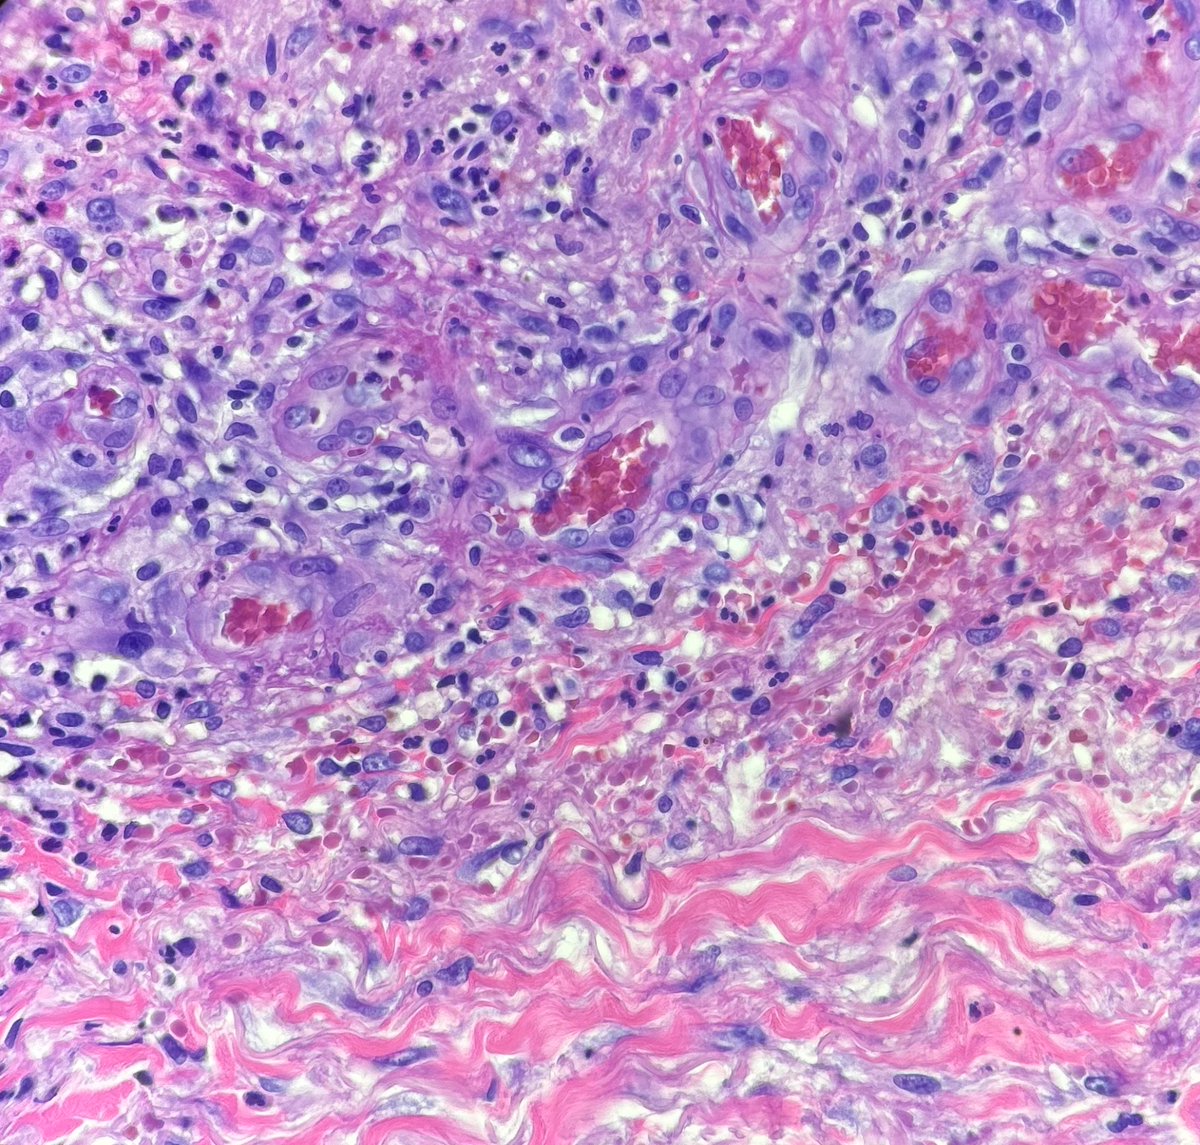

#dermpath #pathology #dermatology Recent case I had of cutaneous involvement by known granulomatosis with polyangiitis. These were photos I shared with the clinician who was concerned for infection.

Recent case I had of cutaneous involvement by known granulomatosis with polyangiitis. These were photos I shared with the clinician who was concerned for infection.